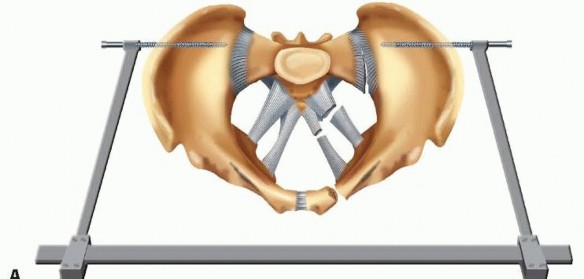

### FIG 5 • The anterior hemipelvis offers two sites for pin insertion: the iliac crest (superiorly) and the supraacetabular region (more inferiorly). A. Profile view. B. Frontal view. Pin placement within the iliac crest is more expeditiously performed and lacks significant regional anatomic hazards. On occasion, this area may be compromised by soft tissue concerns or proximity to fracture planes. In such cases, pin placement within the supra-acetabular region is an option. Pins and frames in this lower position may offer improved access to the abdomen and, unlike pins placed within the iliac crest, are less irritating to anterolateral abdominal soft tissues. 19 In an obese patient, these pins (supra-acetabular) may be better tolerated and less prone to loosening and infection. The dense bone of the supra-acetabular region offers stability of fixation as good as or better than the iliac crest. Some authors investigating the biomechanical performance of these pins (supra-acetabular) demonstrated superior purchase within bone and diminished displacement of posterior portions of the pelvic ring. 12 Because supra-acetabular pin insertion is more time consuming and instrumentation and fluoroscopy dependent, its role as a resuscitative measure is limited. The pelvic antishock clamp (C-clamp) is a posteriorly (or trochanteric) applied device that may offer greater stability to vertically unstable fractures than anteriorly applied frames ( FIG 6).1, 11 It is designed for the emergent treatment of unstable pelvic ring injuries. The device is indicated in both rotationally and vertically unstable pelvic ring injuries. It is contraindicated in lateral compression injuries and fractures involving comminution of the iliac wing or sacrum. If the device is used in lateral compression-type injuries, it may accentuate the deformity. Use of the pelvic 314 antishock clamp with iliac wing fractures may lead to the pins traversing the fracture sites, subsequently causing internal injury.

### FIG 6 • “Antishock” clam This device, applied posteriorly, may offer more stability to vertically unstable injury patterns than anteriorly applied frames. A. Schematic. B. Case AP radiograph. (A: Modified from Simonian PT, Routt ML Jr, Harrington RM, et al. Anterior versus posterior provisional fixation in the unstable pelvis: a biomechanical comparison. Clin Orthop Relat Res 1995;310:245-251.) Despite advances in contemporary pelvic external fixation, concerns and complications associated with its application remain. Among these include poor patient tolerance, loss of reduction as well as pin tract sepsis, and loosening. In an effort to obviate these, the introduction of a subcutaneous internal anterior fixator has been described. 29 This technique employs either a precontoured rod or plate, which is introduced via small incisions at the level of the anterior inferior iliac spine (AIIS). A subcutaneous tunnel overlying the external oblique fascia is established through which the device is delivered and anchored within the dense bone of the supraacetabular region bilaterally. Close proximity to underlying intrapelvic and neurovascular structures demands an understanding of regional anatomy and proper surgical technique. 16, 30 It is not applicable for resuscitative purposes, as its fluoroscopic and insertion times can be intensive. Attributes include enhanced patient mobilization and low documented rates of infection. Its most unique indication may be in obese individuals. 31 Obligatory removal in an operating room setting remains a relative disadvantage. ## TECHNIQUES